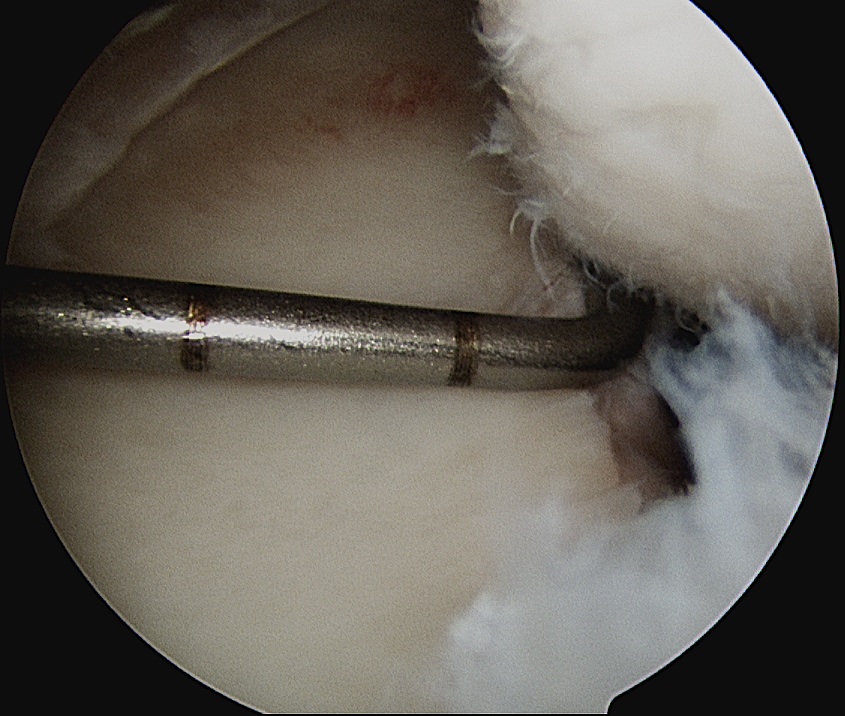

Shoulder Scope Bankart RaspShoulder Stabilisation Labral Mobilisation

Labral mobiliser / rasp

- labral tear can be obvious, but may have partially healed or healed medially

- change camera to anterosuperior portal for better view

- mobilize until can see subscapularis muscle underneath

- need to be able to advance labrum medially and superiorly for repair